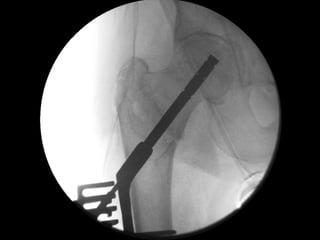

‘Tip-Apex’ fixation maintained

Best bone quality & trabecular lines

Snug fit in drill-hole

Not so snug